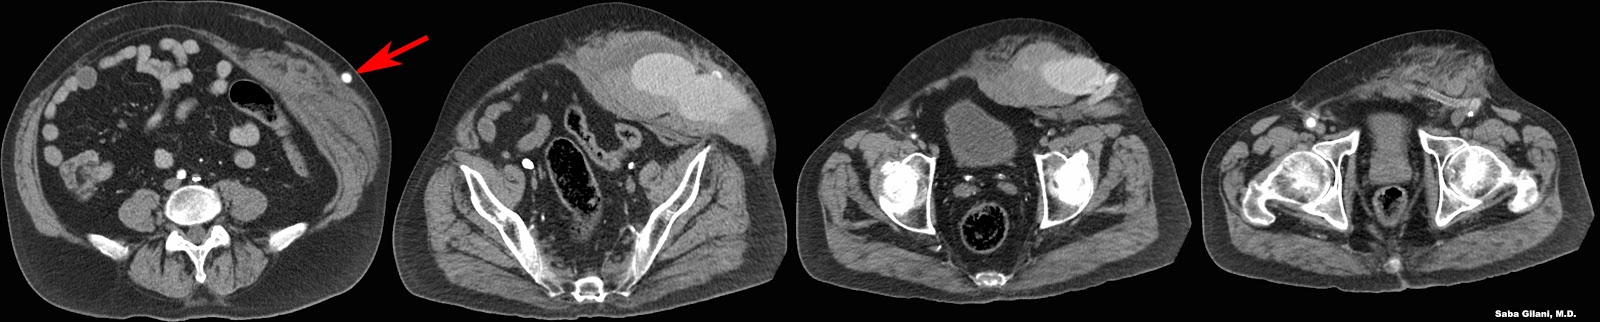

- retrograde embolization of a splenorenal shunt with ethanolamine oleate

- can only be done when a spontaneous splenorenal shunt is present

- maintains patency of TIPS